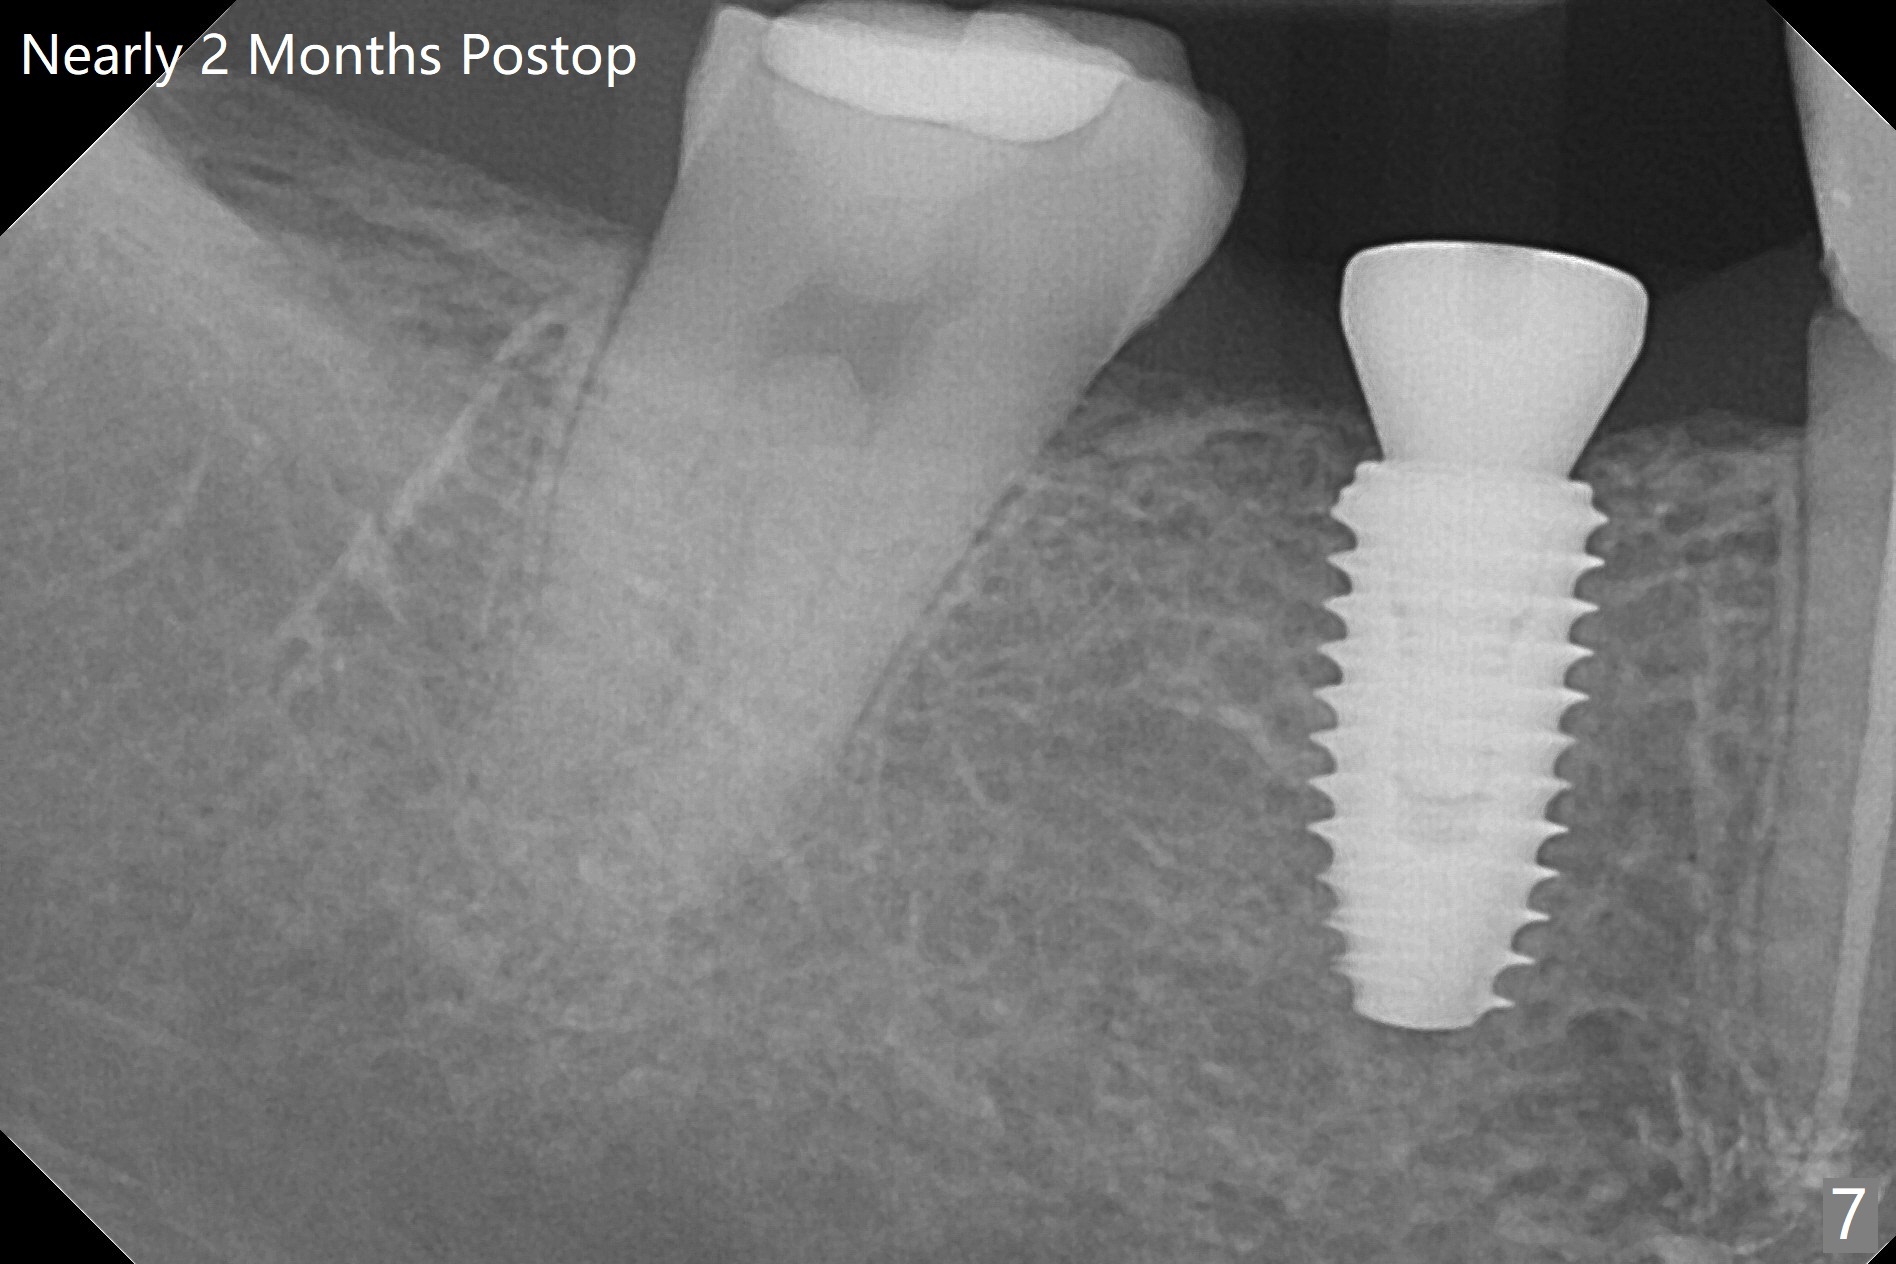

A 5x10 mm implant is placed at #30 with a surgical guide (Fig.1 *) in 10 minutes. The most amazing part of this surgery is that the guide allows you to place the implant at the precise level care-free (~ 1 mm subcrestal, Fig.2,3). Everything happens so quick that when a 5.5x3 mm healing abutment is placed (Fig.4), you are pleased to feel that the implant is stable (Fig.5). You could not ask for anymore. The fearful patient reports no postop pain. The implant is placed as planned (Fig.6, overlap image provided by the guide designer, Jennifer). The patient returns for impression nearly 2 months postop (Fig.7,8). It appears that the implant has osteointegrated without bone loss (Fig.7). The soft tissue is healthy around the just placed cementation abutment (Fig.8 (5.2x4(2) mm)). When the permanent crown is seated initially 2.5 months postop, the mesial contact is slightly tight and the occlusion is high. Bitewing shows the distal open margin (Fig.9 >). After mesial contact adjustment, the patient feels that the occlusion is better. With further occlusal adjustment, the crown is cemented without distal open margin (Fig.10). The patient returns to her home country for 3 months. The implant is doing well 3.5 months post cementation; impression is taken for #14 surgical guide.